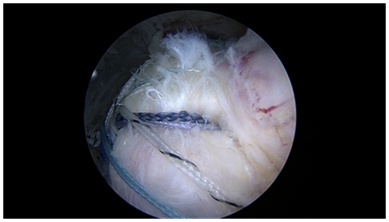

Biceps tenodesis (Figure 8): Arthroscopic supra pectoral approaches to biceps tenodesis that release the sheath are an option for biceps tenodesis, likely because pain relief may be provided by releasing the biceps sheath.24,31 A transosseous approach in this setting reduces anchor use, and obviates the use of a potentially troublesome wound in the axilla. Bone in this area is the most robust in the proximal humerus, and thus readily accessible for strong fixation in anchorless techniques.

Figure 8 Biceps tenodesis: All transosseous suprapectoral biceps tenodesis with tendon grasping sutures.

The biceps may be released, or initially left in situ for this technique. We prefer to release the biceps to allow for an interesting tendon grasping repair. Two tunnels are created with an awl from an anterolateral portal after releasing the biceps sheath. The first tunnel is created from the same portal in the inferior position, just at the superior margin of the pectorals major and above the anterior circumflex vessels. The doubled suture is retrieved through the tendon from an accessory inferomedial portal, and a locking loop is formed utilizing a retrograde passing device. This suture loop is then locked with the lateral suture tail and tied arthroscopcially with the biceps at physiological length from a posterior arthroscopic grasper. The second, more superior tunnel is then created using the arthroscopic tunneler. This double passing suture is then brought through the tendon using a retrograde passing device from the inferomedial portal. Grasping instruments are used to pass the loop over the tendon, creating a strong circumferential grasp on the tendon. The retrograde device is then used to create another locking loop through the circumferential loop, creating excellent fixation with a “cinch loop configuration”. These sutures are then tied arthroscopically with the post lateral. The remaining tendon is removed, and the tendon ends are annealed with the electrocautery.32-38